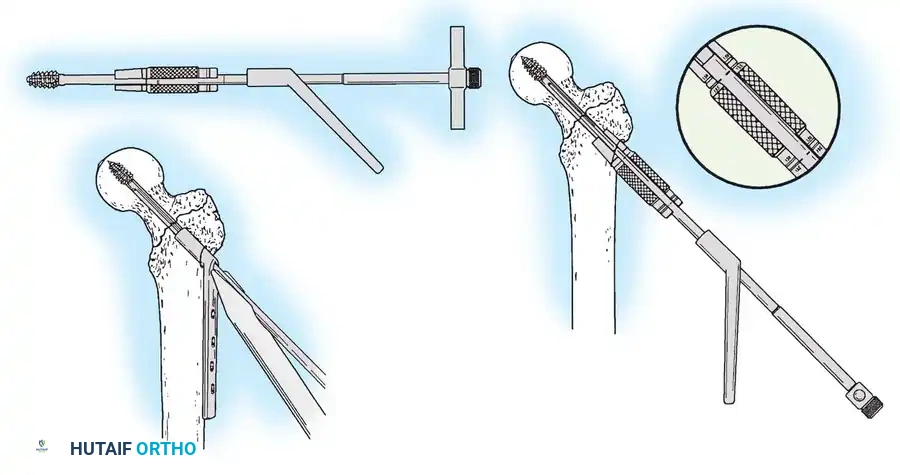

3. Guide Wire Placement

Whether using an SHS or a CMN, accurate placement of the guide wire into the femoral head is the most critical step of the operation.

Insertion of the guide wire. The wire must be positioned centrally in the femoral head on both AP and lateral views.

The Tip-Apex Distance (TAD):

Described by Baumgaertner, the TAD is the sum of the distance from the tip of the lag screw to the apex of the femoral head on both the AP and lateral radiographs. A TAD of less than 25 mm is strongly predictive of successful fixation; a TAD > 25 mm significantly increases the risk of screw cut-out.

4. Reaming and Lag Screw Insertion

Once the guide wire is perfectly positioned, the lateral cortex is opened, and the femoral neck is reamed over the wire.

Reaming of the femoral neck and head over the precisely placed guide wire, preparing the channel for the lag screw.

The lag screw is then inserted. It is crucial not to over-insert the screw, which can penetrate the articular cartilage, nor to under-insert it, which compromises fixation.

Proximal locking of the cephalomedullary nail. The targeting guide ensures accurate trajectory into the femoral neck.